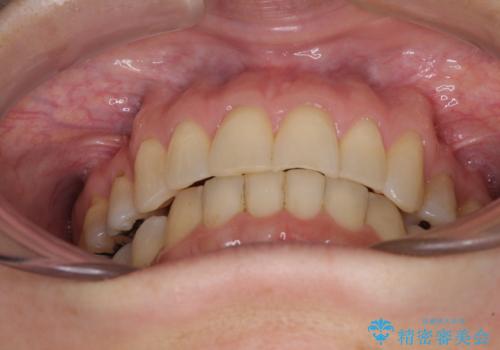

インビザライン・ライトは、製作できるアライナーの枚数に制限があるため、移動可能な量に限りがあります。

軽微な後戻りの治療であったため、十分に治療を行うことができました。

口を開けたときに金属が見えなくなり、患者様には大変満足していただきました。